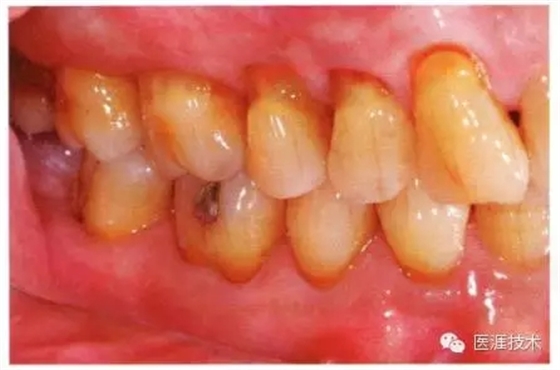

56歲牙周炎男性的臨床照片

正在服用高血壓藥中的56歲男性。菌斑控制得不好。通過牙周探診,全頜有4~6mm的牙周袋,在X光片中可以看到全頜中度牙槽骨吸收,磨牙處一個地方是重度牙槽骨吸收。通過比較牙周病進(jìn)展?fàn)顟B(tài),邊緣部有大范圍浮腫(發(fā)紅、腫脹),和纖維性肥厚。這也可能是服用中的降壓藥的副作用導(dǎo)致的。因為牙齦、牙槽骨比較厚,牙齦呈架子狀。